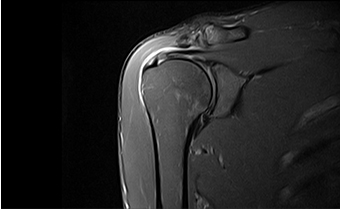

高均匀度磁体

呈现大FOV、偏中心优质图像;实现大范围压脂成像,缩短压脂序列时间